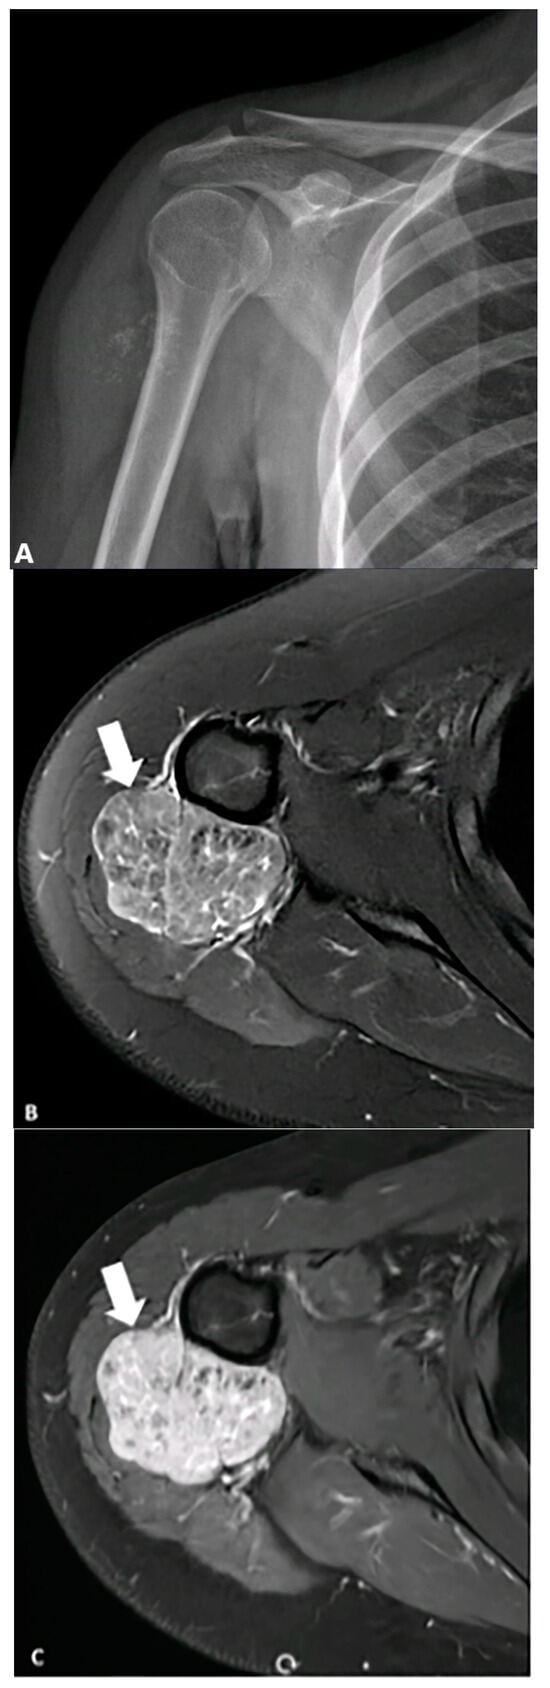

4.8. Tumors of Uncertain Differentiation

- Kwee, R.M.; Kwee, T.C. Calcified or ossified benign soft tissue lesions that may simulate malignancy. Skelet. Radiol. 2019, 48, 1875–1890. [Google Scholar]

- Wilkerson, B.W.; Crim, J.R.; Hung, M.; Layfield, L.J. Characterization of synovial sarcoma calcification. Am. J. Roentgenol. 2012, 199, W730–W734. [Google Scholar] [CrossRef] [PubMed]

- Chotel, F.; Unnithan, A.; Chandrasekar, C.; Parot, R.; Jeys, L.; Grimer, R. Variability in the presentation of synovial sarcoma in children: A plea for greater awareness. J. Bone Jt. Surg. Br. Vol. 2008, 90, 1090–1096. [Google Scholar]

- Liang, C.; Mao, H.; Tan, J.; Ji, Y.; Sun, F.; Dou, W.; Wang, H.; Wang, H.; Gao, J. Synovial sarcoma: Magnetic resonance and computed tomography imaging features and differential diagnostic considerations. Oncol. Lett. 2015, 9, 661–666. [Google Scholar]